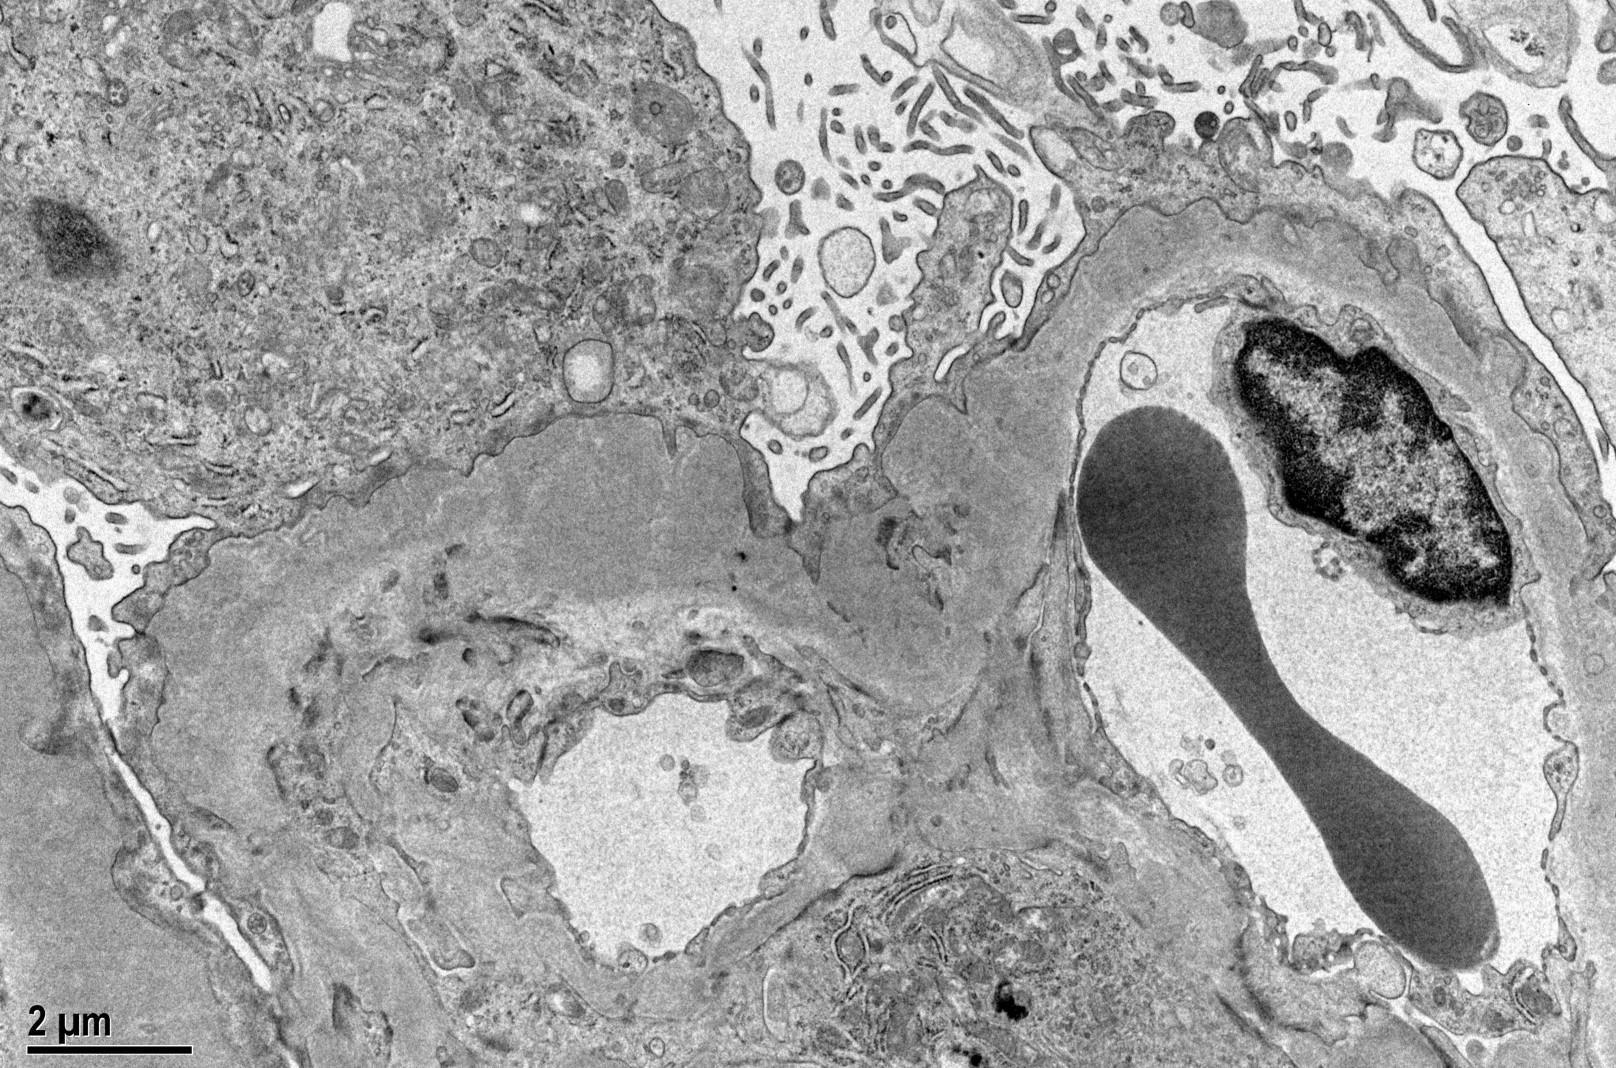

Immunofluorescence microscopy reveals a diffuse granular pattern of immunoglobulin G (IgG) staining along the GBM. The hallmark lesions on electron microscopy are subepithelial electron-dense deposits on the outer aspect of the GBM, effacement of the foot processes of the overlying podocytes, and expansion of the GBM by deposition of new extracellular matrix between the deposits (which are the "spikes" seen with the silver stain). Mesangial and/or subendothelial deposits of immunoglobulin are not seen in primary MN.